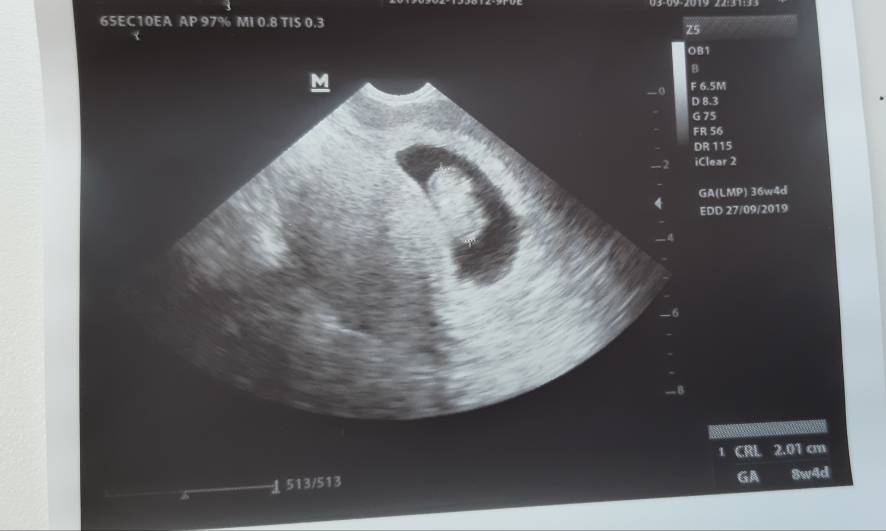

Dziewczyny wychodzę do domu :) A to moje maleństwo [emoji173] Ma 2cm :)Zobacz załącznik 1019101